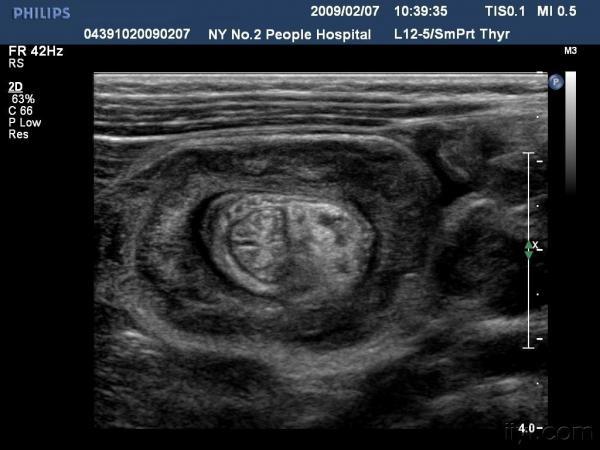

【贴图】肠套叠

患儿哭闹数小时来我院就诊,超声检查发现右侧相当于结肠肝区位置可见“同心圆征”。来和大家分享一下,呵呵。